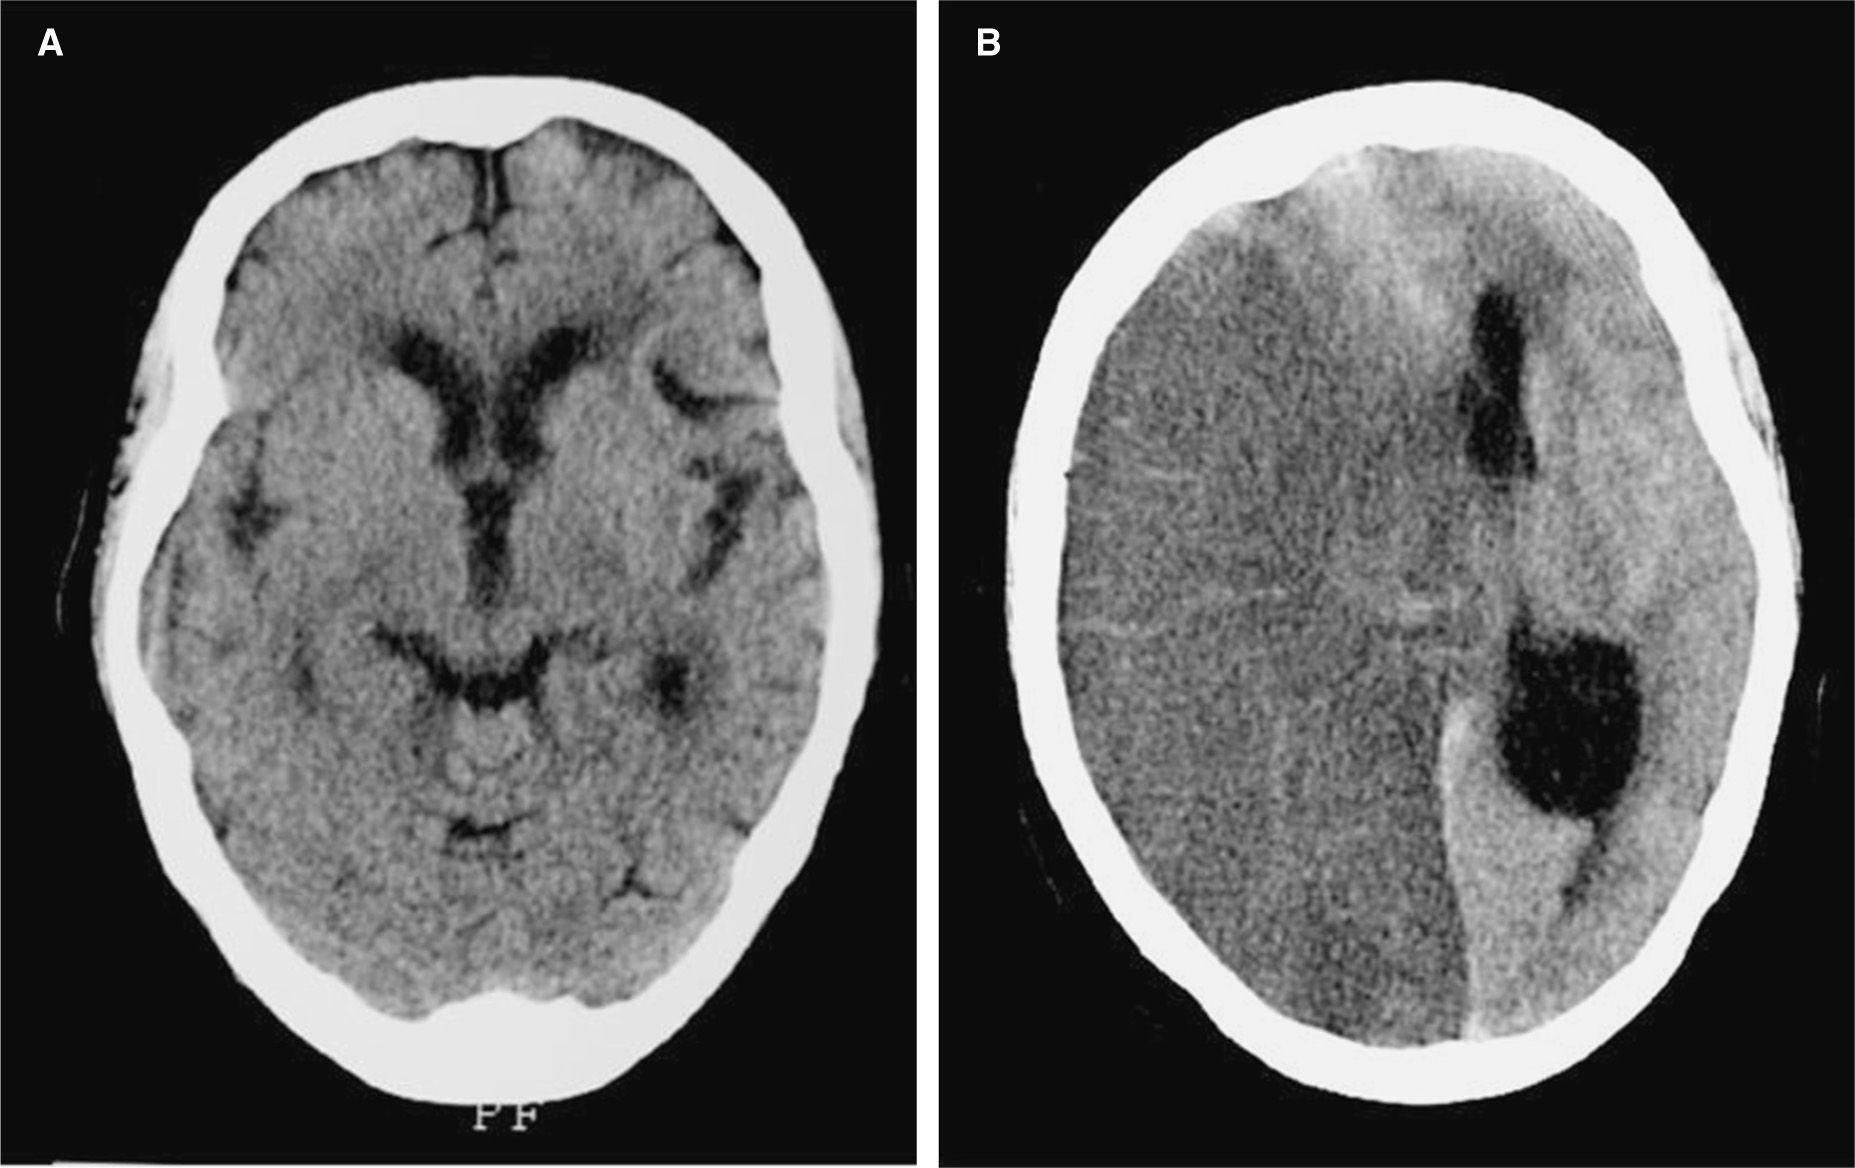

Así como Simón, hay otros pacientes que por golpes en la cabeza o accidentes cerebrovasculares, perdieron el habla. Para esos casos hay un área específica: fonoaudiología. Las fonoaudiólogas entrenan no sólo la recuperación del habla, sino también la deglución, la respiración, y otras funciones que tienen que ver con el tránsito y la boca. Hay prácticas extraordinarias, como la de recuperar la proferencia de un sonido (por ejemplo, de una consonante) con el estímulo de un gajo de limón. Pienso ahora que la sinestesia es el orden natural con el que opera el organismo para captar, interpretar y distribuir la información.